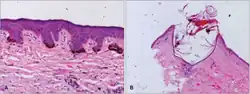

- Skin biopsy